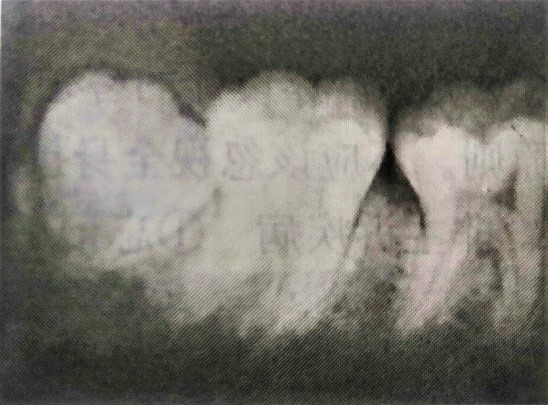

患者,男,18歲。左下后牙脹痛3天,伴張口受限1天。3天前患者自覺左下后牙脹痛,后逐漸咀嚼吞咽時(shí)疼痛加重等癥狀。1天前出現(xiàn)張口受限,患牙無冷熱刺激痛及牙齒浮出感。檢查可見:雙側(cè)面容對(duì)稱,左側(cè)面部咀嚼肌處無紅腫熱痛等表現(xiàn),張口度約一指半。左下8牙冠咬合面顯露一部分在口腔中,其余部分被遮蓋在齦瓣之下。可探及牙體,有盲袋,周圍軟組織發(fā)紅,齦瓣邊緣糜爛,觸痛明顯,且有少量膿液自盲袋溢出。左下6近中牙體變色,探診有深齲洞,洞底探診酸痛明顯,刺激消除疼痛消失,未探及穿髓孔。X線片顯示左下8近中阻生,左下6近中透射區(qū)未達(dá)髓腔。檢查情況及X線片見下圖:

(2)X線片顯示透射區(qū)未達(dá)到髓腔。